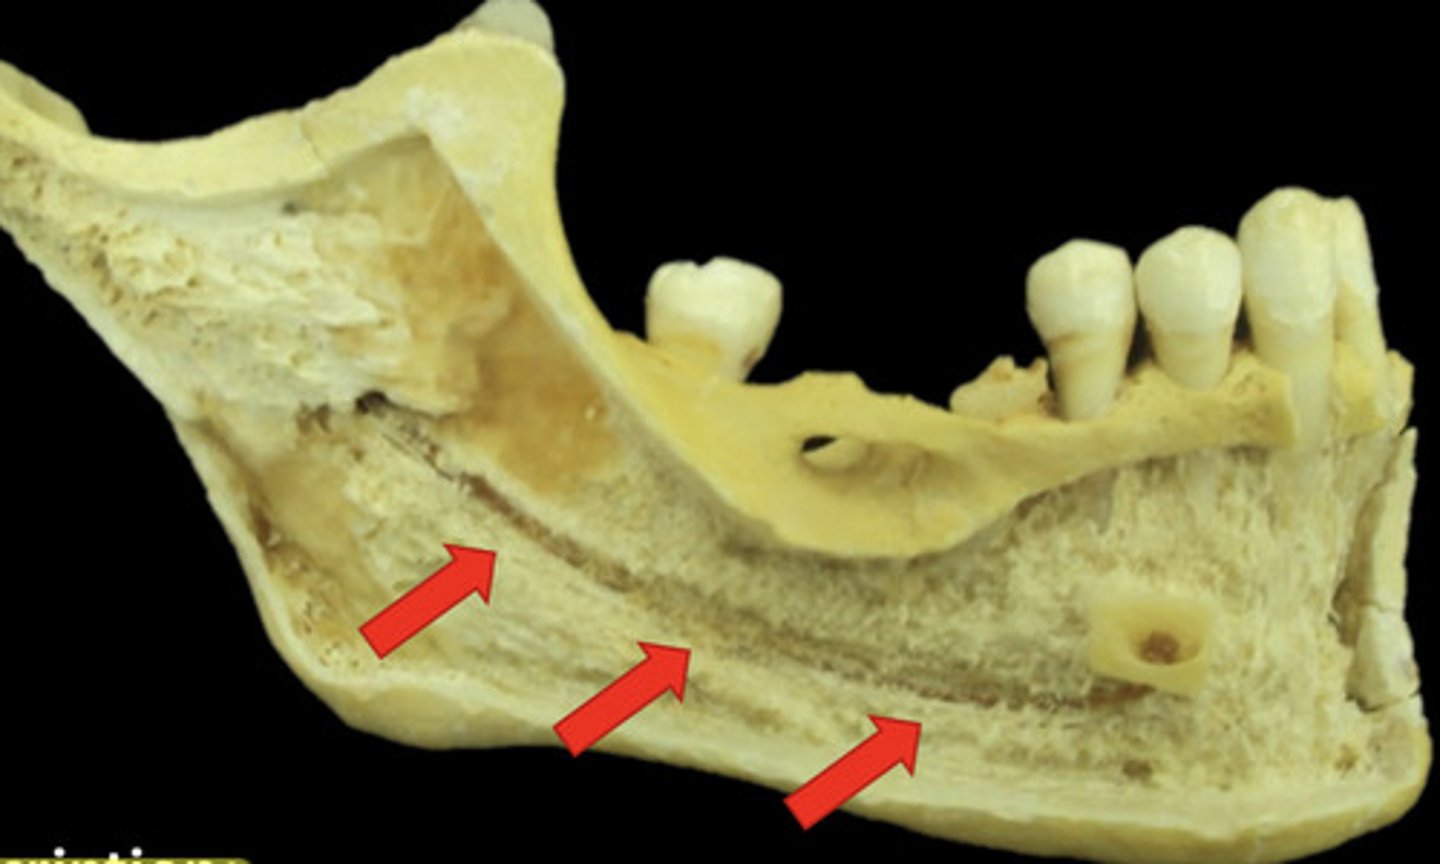

What are nutrient canals?

anatomic structures of the alveolar bone through which neurovascular elements transit

information on nutrient canals

little lines of radiolucency found in maxillary & mandible

What do nutrient canals look like radiographically?